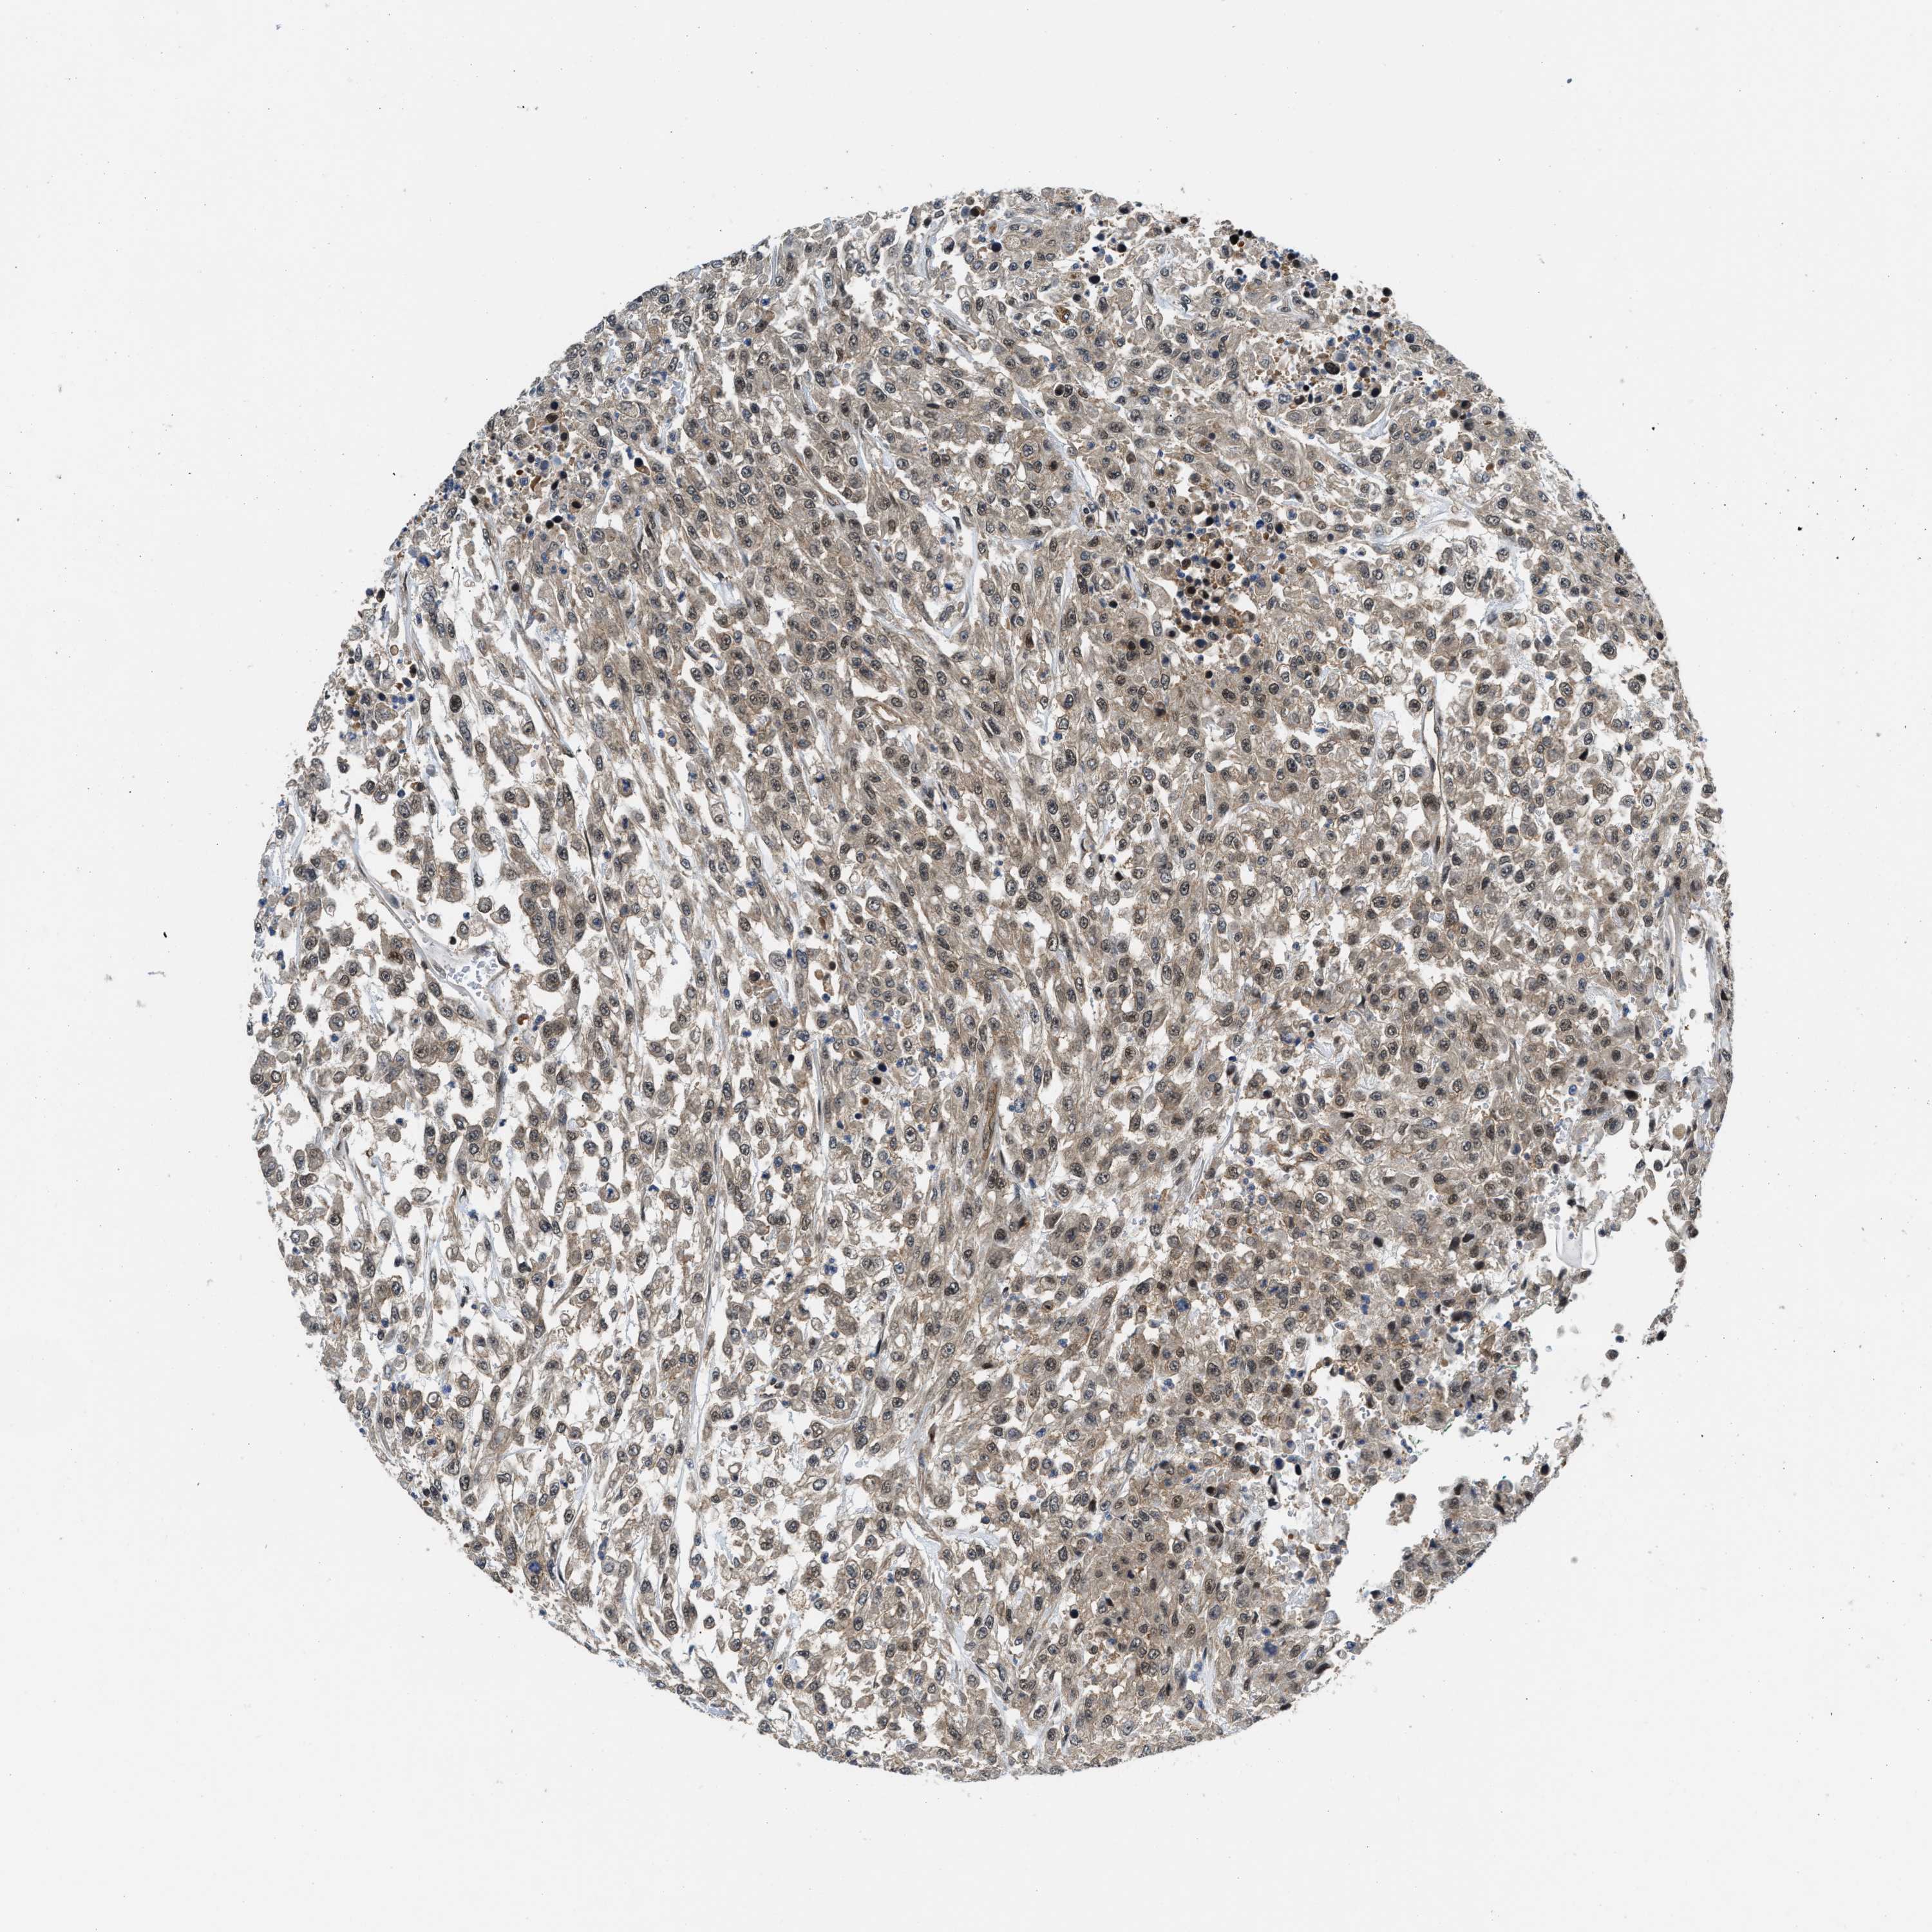

UROTHELIAL CANCER - Protein expressioni

A mouse-over function shows sample information and annotation data. Click on an image to view it in a full screen mode. Samples can be filtered based on level of antibody staining by selecting one or several of the following categories: high, medium, low and not detected. The assay and annotation is described here.

Note that samples used for immunohistochemistry by the Human Protein Atlas do not correspond to samples in the TCGA dataset.

Antibody stainingi

Antibody staining in the annotated cell types in the current human tissue is reported as not detected, low, medium, or high, based on conventional immunohistochemistry profiling in selected tissues. This score is based on the combination of the staining intensity and fraction of stained cells.

Each image is clickable and will lead to virtual microscopy that enables deeper exploration of all samples and also displays staining intensity scores, fraction scores and subcellular localization as well as patient and tissue information for each sample.

Antibody HPA016867

Antibody HPA018271

Urothelial carcinoma, Low grade

Urothelial carcinoma, High grade